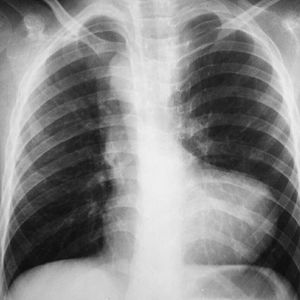

TOF is the most common cyanotic congenital heart disorder. It has four cardinal features, Right ventricular hypertrophy, ventricular septal defect, obstriction of right ventricular outflow, and aortic overriding. Plain X-Ray shows boot shaped heart with upturned heart apex. Treatment is by creating a shunt.